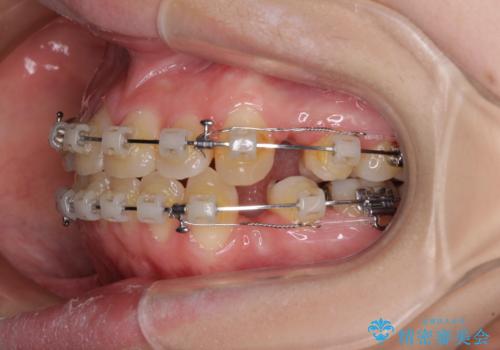

- 矯正装置

- クリアブラケット

- 上下前歯が前方に飛び出しているとのことで来院された患者様です。

上下左右第一小臼歯4本を抜歯して、積極的に口元を引っ込めるよう、ワイヤー装置にて矯正治療を行うこととしました。

口元の突出感は著しく改善され、横顔の印象が大きく変化しました。